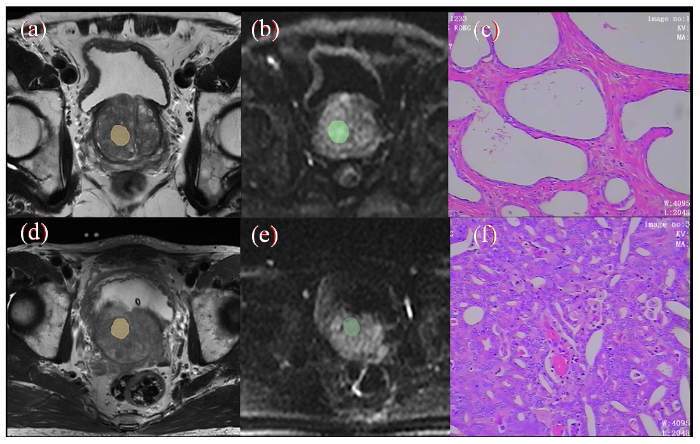

图1

病灶勾画示意图及病理组织染色图. (a)~(c)为PCa图像,(d)~(f)为BPH图像;(a)/(d)显示T2WI上勾画ROI;(b)/(e)为DWI上勾画ROI;(c)/(f)显示病理组织染色图(HE×100)

Fig. 1

Schematic diagram of lesion delineation and pathological tissue staining (a)~(c) are PCa images, (d)~(f) are BPH images; (a)/(d) display ROI delineated on T2WI; (b)/(e) draw ROI on DWI; (c)/(f) display pathological tissue staining image (HE×100)